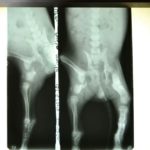

Francesca took the pup to her vet, who x-rayed the pelvis and said that nothing could be done for her. After two weeks of rest at the clinic, the puppy was somehow up and moving about, even playing!

Dr. Calderon took new x-rays, and her injuries are consolidating, so he recommended not to do anything for the moment. The puppy may need an amputation later when she has grown.